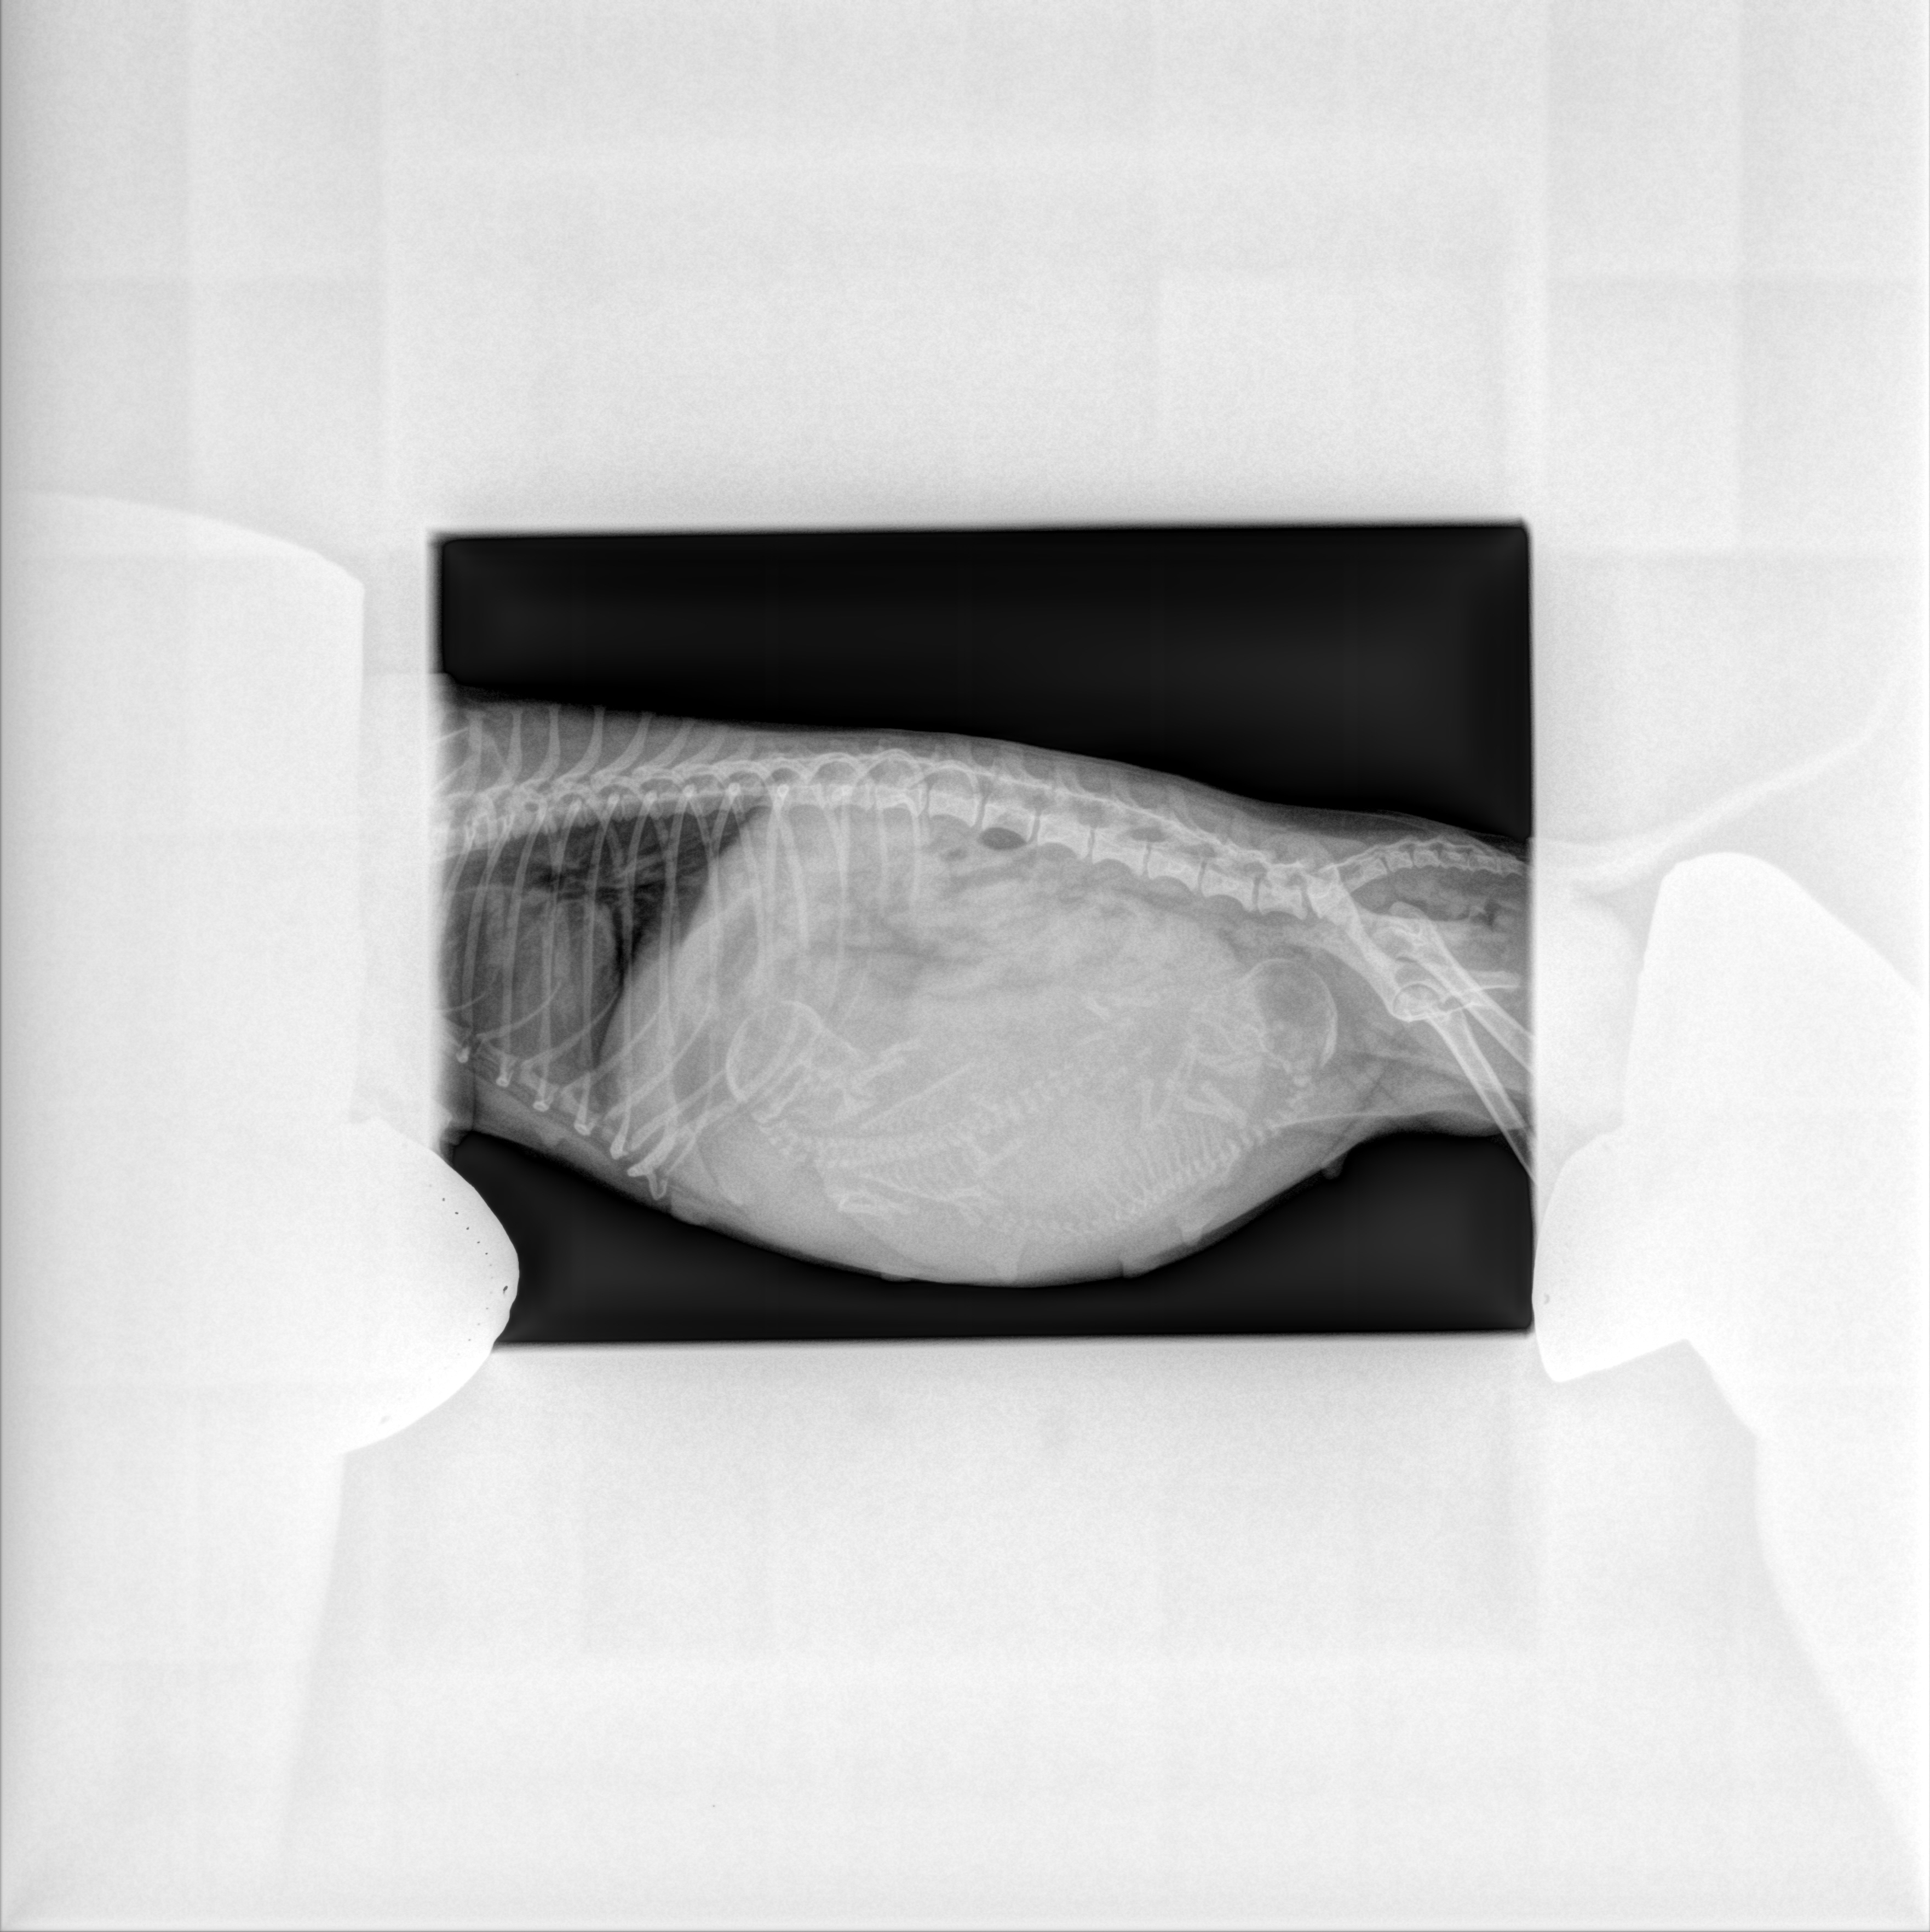

Une radiographie, après 45 jours de gestation (moment où a lieu l’ossification du squelette des chiots), pourra être programmée afin de compter plus surement et définitivement les chiots.